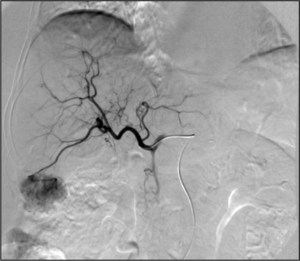

- Kidney cancer: kidney tumors such as renal cell carcinoma can be treated with image-guided ablation (RFA, MWA, cryotherapy) with similar results to partial nephrectomy. Generally, surgery via an either partial or total nephrectomy (removal of kidney) is most often curative but for patients with a smaller lesion or who are not ideal surgical candidates, radiofrequency or cryoablation ablation can be a curative option.[75] Advantages of cryoablation include the ability to visualize the ice ball as well as use more than one probe simultaneously to create the desired ice ball shape. Benign kidney tumors such as angiomyolipomas can be treated with transarterial embolization to shrink the tumor size and reduce the risk of rupture/bleeding. Other embolizations are also performed for symptom relief or prior to surgery to reduce bleeding.[76]